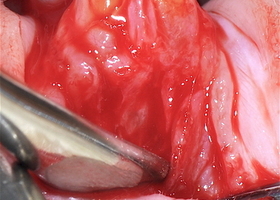

- Далее пациентам проводилась зубосохраняющая операция – цистэктомия с одномоментной резекцией верхушки корня (РВК) зуба с заполнением костной полости остеопластическим материалом.

- 43 пациента были разделены на 2 группы в зависимости от использованного остеопластического материала.

- I группа (22 человека) – в качестве остеопластического материала использовали деминерализованную спонгиозу «Лиопласт»® (Самарский банк тканей, Самара).

- II группа (21 человек) – для заполнения костной полости применяли синтетический материал «CrossBone»® (Biotech, Франция).

Компьютерные томограммы 22 пациентов I группы показали замещение костного дефекта регенерата через 3 месяца после операции: определяется формирующийся трабекулярный рисунок границы костной полости не дифференцируются от окружающих тканей.

На КТ у 21 пациента II группы на всех сроках наблюдения отчетливо видны гранулы материала, которые не были подвержены резорбции.

Клинический пример №1

Пациентка Т., 35 лет. Обратилась на прием с жалобами на ноющую боль, чувство дискомфорта в области зуба 1.4.

Основываясь на данных клинико-рентгенологического исследования был поставлен диагноз «хронический апикальный периодонтит 1.4» (рис. 4,а).

Пациентке была проведена операция цистэктомии с одномоментной резекцией верхушки корня зуба с последующим заполнением костной полости деминерализованной спонгиозой «Лиопласт»®.

Клинический пример № 2

Пациент М, 22 года обратился на прием с жалобами на ноющую боли, чувство распирания в зубе 4.1.

Основываясь на данных рентгенологического исследования был поставлен диагноз «хронический апикальный периодонтит 4.1».

На рисунках 5(б) и 5(в) отчетливо видна костная полость, заполненная гранулами материала «CrossBone»®, который не меняет свою конфигурацию, не резорбируется и не замещается костной тканью на протяжении всего срока наблюдения.

Отчетливая дифференцировка этого материала от губчатого вещества сохраняется и через 6 месяцев после операции.